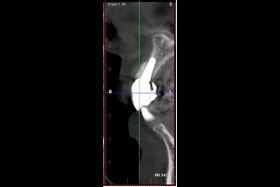

治療後,X光片。